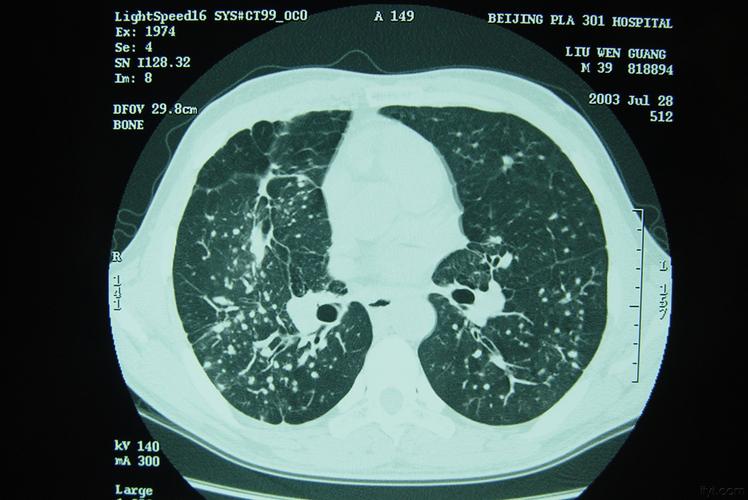

矽肺影像

矽肺影像,矽肺影像图片

矽肺

矽肺|肺及下呼吸道-医影在线-专业权威的医学影像交流

矽肺影像图片

矽肺结节

矽肺CT

矽肺病

矽肺三期

矽肺病图片

矽肺ct图片